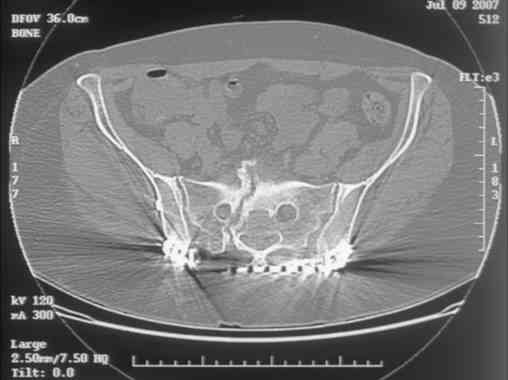

Here is a magnified view. Sorry about the quality but the CT was scanned into our system.

dave